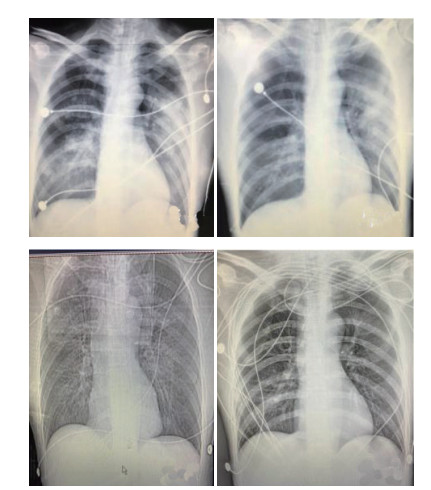

随着精细化治疗,患者病情逐渐好转,7月10日胸片心影形态正常,片絮影吸收(图 9),心脏超声:左心EF上升至45%(表 3)。停用血管活性药物,尿量及乳酸正常,在ECMO辅助72 h后顺利撤机,当天即外出行高压氧治疗。患者神志逐渐清醒,于7月12日脱离呼吸机拔出气管插管,于7月15日顺利转出EICU。未留下神经系统后遗症,CPC评分1分。

| A-C依次为7月8日至7月11日胸片 图 9 患者胸片 Fig 9 Chest CT of the patient |